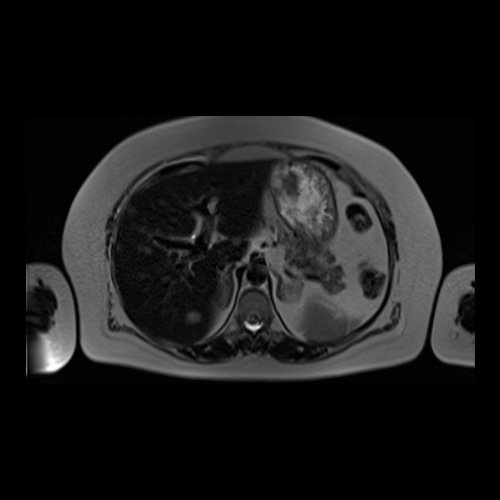

RMI abdomen y pelvis con contraste EV (14/02/26): En las bases pulmonares se visualizan atelectasias laminares bibalsales. No se identifica derrame pleural. El hígado es de forma, tamaño y situación normal. La superficie es lisa, los bordes son agudos. Se observan múltiples lesiones sólidas de distribución difusa, levemente hiperintensas en T2, con restricción en difusión y realce homogéneo tras la administración de contraste EV, la de mayor tamaño de 15 mm en segmento VII. Sugiero conocimiento histológico. La vía biliar intra y extrahepática es de calibre conservado. La vesícula biliar es de forma y situación habitual, sus paredes son finas y no presenta imágenes hipointensas en su interior, que sugieran la presencia de litiasis. El bazo es de forma, tamaño y situación normal, sin efectos de masa focales. El páncreas es de forma, tamaño y situación normal, sin efectos de masa. El Wirsung es de calibre conservado. Glándulas adrenales de forma, tamaño y situación normal, sin efectos de masa. Ambos riñones son de forma, tamaño y situación normal, con adecuada diferenciación córtico subcortical. No se observan alteraciones a nivel de la vía excretora. No se observan adenomegalias retroperitoneales ni intraperitoneales. La aorta abdominal, las arterias iliacas primițivas, internas, externas y femorales son de trayecto y calibre normal La vena cava inferior, las venas ilíacas primitivas, internas, externas y femorales son de trayecto y calibre normal. No impresionan alteraciones a nivel del tracto gastrointestinal. La vejiga es de paredes finas, normalmente distensibles, sin evidencia de lesiones endoluminales ni parietales. Mioma transmural en hoja anterior de útero que mide 55 x 47 mm sin signos de complicaciones. Imagen ovalada de contenido líquido que mide 65 x 52 mm en el espesor del tejido celular subcutáneo de región antero-superior de muslo derecho, por delante de músculo sartorio, que no presenta realce tras la administración de contraste EV.

RMN de abdomen con contraste endovenoso (14/02/26) Corte axial (T2): múltiples lesiones sólidas de distribución difusa, levemente hiperintensas.

RMN de abdomen con contraste endovenoso (14/02/26) Corte coronal (T2): adenoma suprarrenal izquierdo; lesión hepática redondeada hiperintensa redondeada en segmento VII.